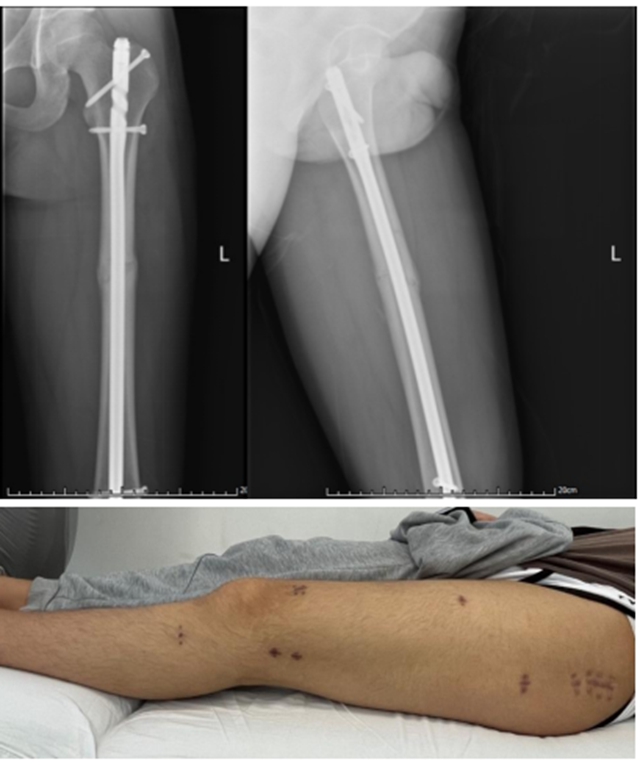

(双反牵引手术切口)

传统手术:切口大,软组织损伤严重,造成患者出血多、术后疼痛重、恢复慢、住院时间长、治疗费用高。

微创手术:切口小、出血少,疼痛轻、恢复快、住院时间短!

在“双反牵引”理念的指导下,绝大多数下肢骨折都可以应用双反牵引复位器达到微创的手术效果。